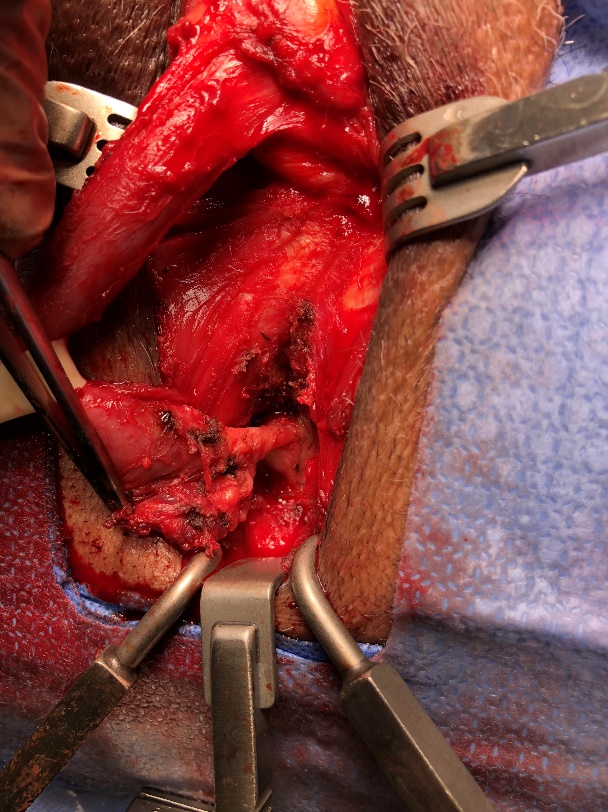

La técnica transvesical (de O’Connor) se basa en una cistotomía amplia desde el domo vesical hasta llegar a la fistula por posterior, con adecuada visualización y eventual cateterización de los uréteres (Figura 25). Se debe realizar una cuidadosa disección del plano vesicovaginal (Figura 26). Cierre de la pared vaginal con material reabsorbible 3-0 y luego cierre de la vejiga con similar sutura (Figura 27). Se puede además movilizar un colgajo de peritoneo o epiplón que se interpone entre ambas suturas.